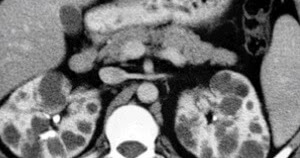

Lenf nodu izlenmiştir ne demek merhabalar. Her iki koltuk altında da sağ aksillada 40x10 mm korteksi simetrik kalın ekojen yağlı hilusu bulunan oval şekilli ve sol aksillada 48x10 mm boyutlarında korteksi ince ekojen yağlı hilusu bulunanoval şekilli lenf nodu tespit edildi. Genellikler lenf nodlarının genişlemesi boyun koltuk altı kasık ve çenenin altı gibi lenf nodlarının bulunduğu yerde gerçekleşir. Meme kanseri ameliyatında koltuk altı lenf bezleri çıkartılarak aksiller lenf nodu diseksiyonu hem gidişat için durum tespiti yapılmış hem de meme kanserinin önemli yayılma yollarından biri ortadan kaldırılmış olur.

Sağ aksiller bölgede en büyüğü 1cm çapında lenf nodu izlenmiştir bunun için ne yapılması gerekiyor nasıl bir araştırılma yapılması lazım 1 cm lenf nodu tehlike arz ediyormu nasıl bir yol izlemem gerekir. Lenf nodu nedir lenf nodu ne demek lenf nodu anlamı lenf nodu hakkında bilgi bulunduran paylaşım platformu. Reaktif lenf nodu koltuk altı göğüs karın içi bazı organlarda kulak arkası ve boğazda çenede bulunur. Meme kısmen alınsa da tümüyle alınsa da bu dokuların çıkartılması gerekebilir.